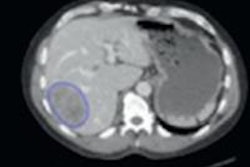

A standard CT scan (top left) with the tumor outlined in white. With the TexRAD software applied, it is possible to analyze the tumor's texture at a fine (red), medium (green), and coarse (blue) level. Image courtesy of bowel cancer case analysis from University College London Hospital.Colorectal cancer kills more than 16,000 people a year in the U.K., making it the second-most common cause of cancer death after lung cancer.

In one study, texture analysis was found to enable early diagnosis of those bowel cancer patients who weren't responding to standard cancer therapies better than other available tumor markers. The same TexRAD markers also showed the ability to assess at an early stage the likelihood of survival, distinguishing patients who will have a good prognosis from those having poor prognosis, the authors report.

In a series from University College London Hospitals (UCL), for example, researchers analyzed baseline PET/CT scans and then followed up patients for an average of three years. The tumor image analysis enabled them to accurately predict patient survival, Ganeshan, Dr. Ming Young Simon Wan, and colleagues wrote in their RSNA abstract (SSQ06-05).

The image filtration-histogram technique was used to assess the CT images, and the investigators also measured FDG uptake (SUVmax) on PET, determining clinical stage using surgical histology and imaging data.

The research team grouped the patients by stage: stage I-III rectal cancer, stage I-III colon cancer, and metastatic stage IV cancer colorectal cancer. Median follow-up for surviving patients was 47.9 months (minimum 12 months). For patients with stage I-III rectal cancer (n = 42), CT texture analysis (coarse skewness, p = 0.011), SUVmax (p = 0.012) and clinical stage (p = 0.006) were the best predictors of survival.

The only independent predictor of survival (p = 0.003) was a significant interaction between skewness and clinical stage. For patients with stage I-II and stage III cancers, texture analysis (unfiltered kurtosis, p = 0.001) and T stage were the only significant survival predictors. And for stage IVb disease, texture analysis (fine kurtosis) was again the only significant predictor of survival.